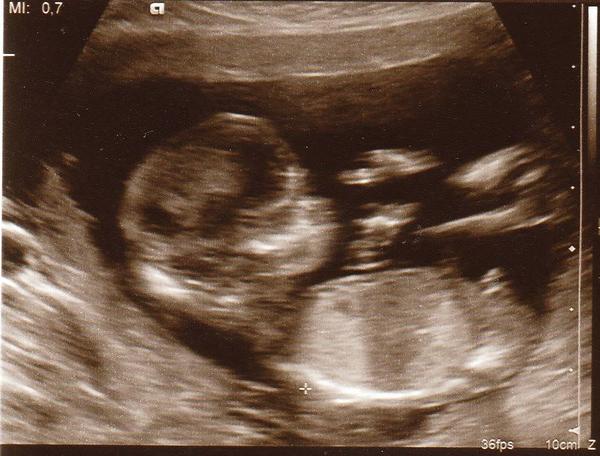

Je to holčička nebo chlapeček? Foto ultrazvuku

Ahoj maminky a budoucí maminky 😉 Prosím, poradila byste mi některá, co vidíte na fotce z ultrazvuku ve 20. týdnu za pohlaví? Určitě jste foteček viděly už mraky, proto vás žádám o radu...Nechci nikoho ovlivnit, proto svůj tip řeknu později 🙂 Děkuju moc!!!

Holčičku bychom tááák moc chtěli, ale jednou asi v 17. tt nám řekli, že to vypadá na chlapečka a teď ve 21. týdnu zas prý na holčičku, ale že by to chtělo ještě jednou potvrdit...

Kluk, máme velmi podobnou fotku už a řekli nám 100 % kluk

@slunicko707 já bych řekla holcicka